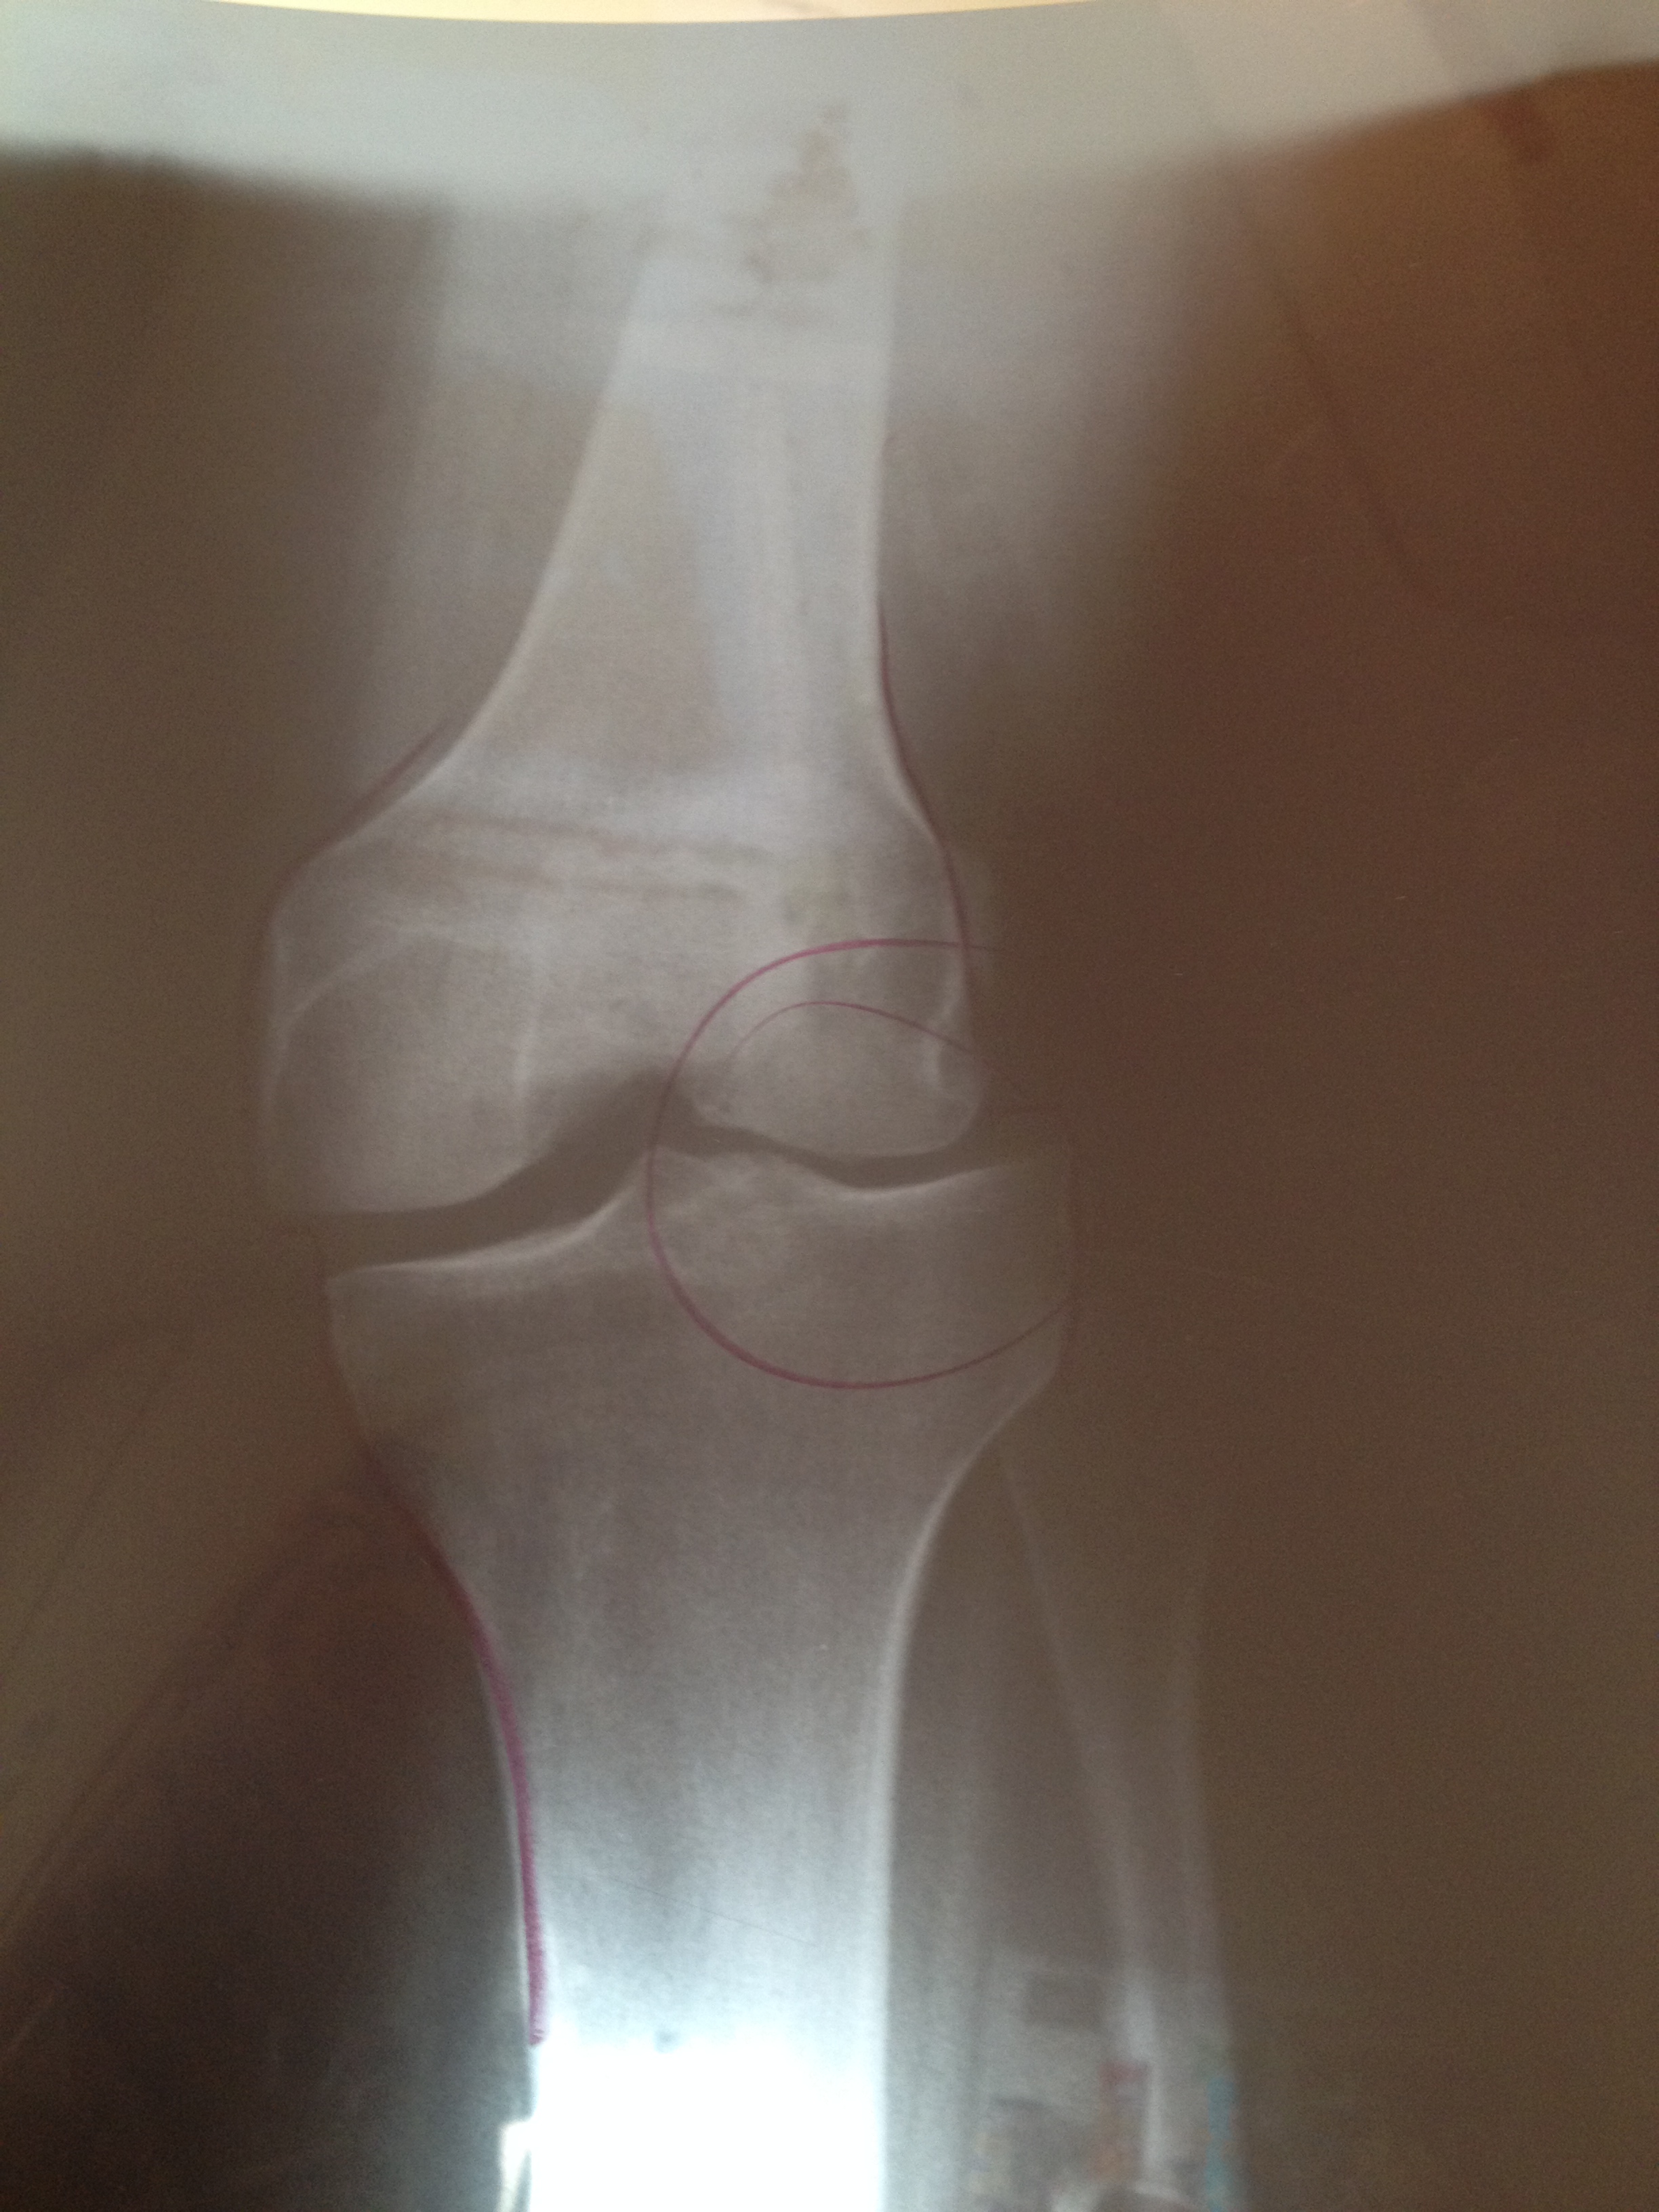

About the only problem I have is my right knee. It has been off center since I had a tripping incident when the kids were younger and we were at a roller skating rink. A young person stopped short in front of me and in order to avoid rolling over them I did a quick pivot and my knee didn’t quite make the same movement. And then there was that time that I tripped down the back steps and actually broke my kneecap.

I can tell you it is no fun being in a leg brace, even one that is bendable. I am not really coordinated when it comes to crutches either. So my leg does occasionally ache but I think having 70 pounds less to carry around helps with that too.

Happy belated Birthday! Ouch – I dread looking at knee X rays but then read that your injury happened some time ago.